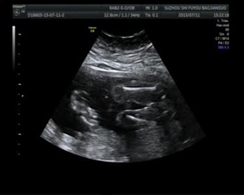

醫(yī)學影像學可以作為一種醫(yī)療輔助手段用于診斷和治療,也可彩超

彩超(3張)

以作為一種科研手段用于生命科學的研究中。診斷主要包括透視、放射線片、CT、MRI、超聲、數(shù)字減影、血管造影等。治療主要應用為介入治療、放療等方面。